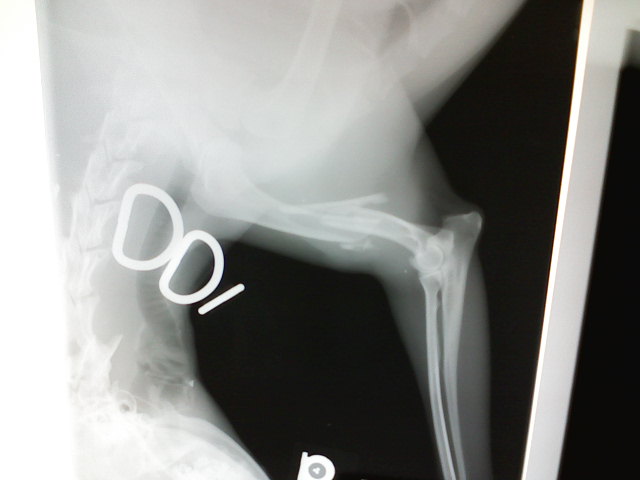

Here is a picture of the x-ray…

as you can see, she shattered it. He was able to put her all back together except for one piece. She has a big pen running length wise in her bone and wires holding everything together.